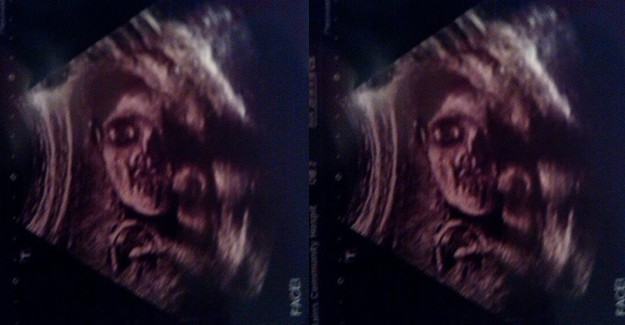

1991’de çekilen, gerçek bir ultrason görüntüsü

Bebeklerini görme heyecanıyla doktora gidip ultrasonda bu görüntüleri gören ebeveynlerin korkmuş olabileceğini tahmin ediyoruz.